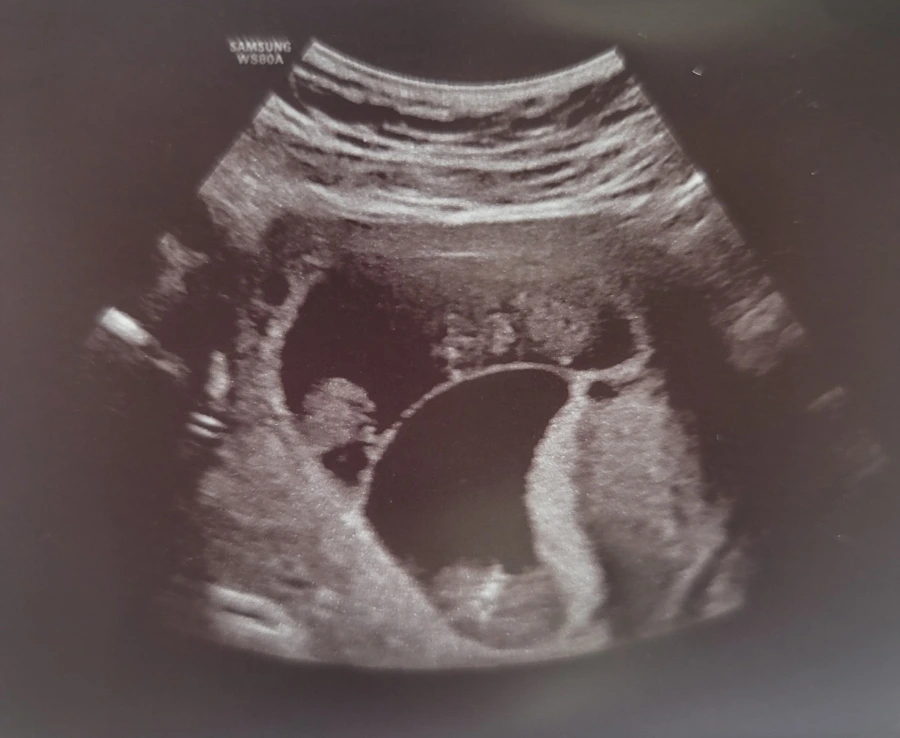

진료의뢰서를 가지고 대학병원으로 첫 진료를 보러갔다. 난임병원도 매번 예약환자로 넘실거리고 대기시간 1시간은 기본이었는데 대학병원은 역시 차원이 달랐다. 복잡하지만 잘 정돈된 병원에서 영상제출, 기록지 제출, 초진 상담 등등 절차를 차근차근 마치고 초음파실에서 세 아가들을 확인했다. 모두 7주 4일, 7주 6일 크기로 비슷비슷하게 자라고 있었다.

이제 임신 9주에 접어들었고, 지긋지긋한 질정과 배주사도 드디어 끝났다. 이번 주차의 초음파 검사에서도 세 아기는 무사히, 그리고 비슷하게 자라고 있었다. 9주 2일, 4일, 5일 그리고 맥박도 166~171로 정상범주였다. 12주차 정밀 초음파 일정을 잡으면서 교수님은 재밌는(?) 제안을 하셨다. 다음달에 초음파학회가 있는데, 학회에서 초음파 시연을 해줄 수 있겠냐는 거였다. 회사 다니면서 학회 관련 비용처리만 해봤지 학회를 직접 가본적은 없었는데 흥미가 확 생겼다. 아가들이 무사히 잘 있나 매주 보고싶은게 초음파인데, 학회에서 초음파를 또 볼 수 있으니 안 할 이유가 없잖아? 어차피 가서 배만 보여주면 되는데 못할게 어딨어 하는 생각에 제안 하시자마자 하겠다고 했다. 이런저런 설명을 해주시면서 소정의 사례비도 있다고 하셨다. 오와 대박이네. 좋아요 좋아요 시연 할래요 교수님!